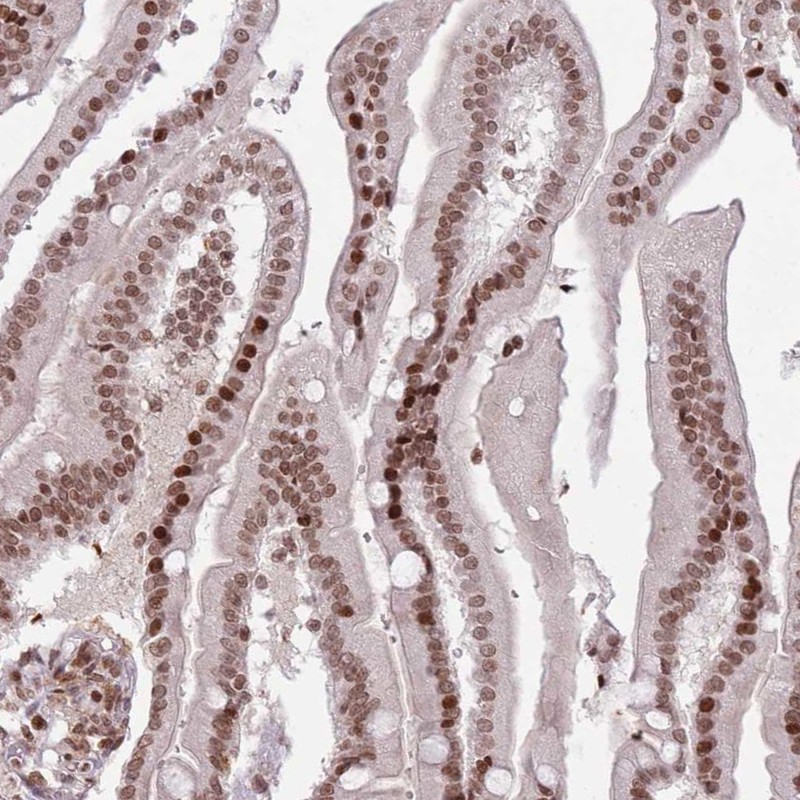

Immunohistochemical staining of human duodenum shows strong nuclear positivity in glandular cells.